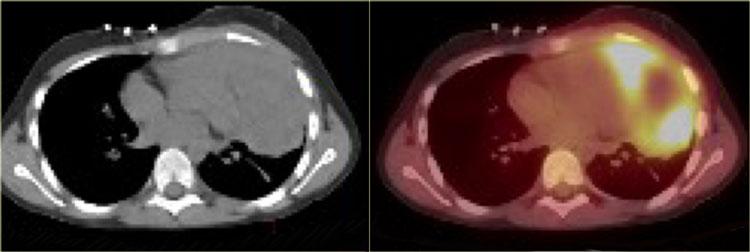

Trên CT, tăng sản biểu hiện là sự phì đại lan tỏa của tuyến ức, với sự bảo tồn hình dạng tam giác bình thường.

Định nghĩa tăng sản tuyến ức là thể tích tuyến ức tăng > 50%.

CT, MRI hoặc PET không thể phân biệt tăng sản phục hồi với thâm nhiễm tuyến ức do khối u.

Sự vắng mặt của các bệnh hoạt động khác và sự giảm dần kích thước tuyến ức trên các lần chụp CT nối tiếp hỗ trợ chẩn đoán tăng sản phục hồi.

Tuyến ức thường trở về kích thước bình thường trong 3 đến 6 tháng.